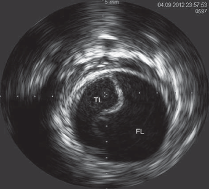

what is happening in this image

is iFR or FFR with medication

FFR is used with medication

one sided occlusion

Eccentric

completely surrounded or encapsulating lumen

concentric